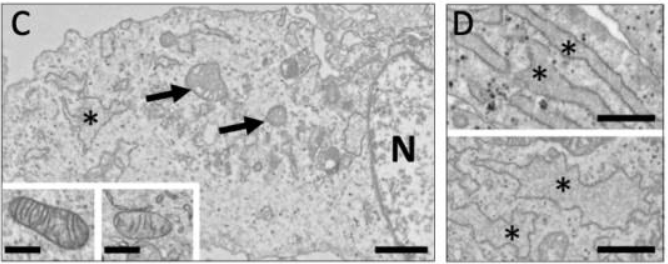

In some TARDBP mutations, it has been found that mutations in genes may affect mitochondrial metabolism and endoplasmic reticulum [6]. To ascertain the impact of the A382T mutation in the TARDBP gene on cell function, researchers analyzed the proteomes of the diseased and wild-typed fibroblasts. Examination of the study's data showed that cytoskeletal dysregulation and impaired mitochondrial activity may be present in ALS fibroblasts. In order to sustain axonal stability, cis- and retrograde transport, and neuronal communication, axonal projections of motor neurons are lengthy and they depend on the health of the neuronal cytoskeleton and mitochondria. Neuronal function is severely impacted by the development of protein aggregates containing components of the cytoskeleton as well as mitochondrial dysfunction [7]. The primary ultrastructural anomalies are found in fibroblasts from ALS patients. The degree of morphological variation in mitochondria is higher; some are noticeably larger with crooked or over-branched cristae, while others have a significant number of decreased cristae. Also, compared to CTRL fibroblasts, endoplasmic reticulum pools in ALS cells are enlarged and irregularly shaped, indicating that the unfolded or misfolded polypeptides are accumulated in the lumen, as seen in Figure 2.

It can be concluded that genetic mutations affect the metabolism and the structure of mitochondria and thus the development of neurons.

Figure 2. (C) Electron micrographs of fibroblasts from ALS patients.

*Endoplasmic reticulum; N, the nucleus.

A mitochondrion is shown by an arrow. Scale bar: 1 mm. Inserts display a mitochondrion from a control (CTRL) and an ALS fibroblast, respectively (right). 500 nm, insert bar. (D) Endoplasmic reticulum images taken under an electron microscope of CTRL (up) and ALS (down) fibroblasts. Scale bar: 1 mm.